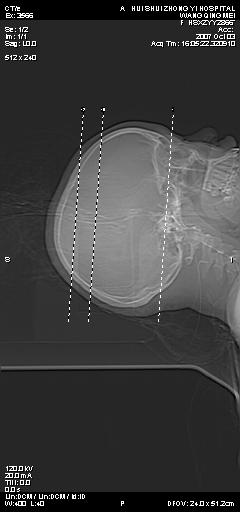

标题: CT9947:女,20岁,妊娠9个月,突然癫痫症状 [打印本页]

标题: CT9947:女,20岁,妊娠9个月,突然癫痫症状

双侧脑白质缺血缺氧性改变,并高度可疑“蛛网膜下腔出血”。

后可复性脑病,

考虑 妊娠子痫或妊高征

双侧脑白质缺血缺氧性改变.

考虑先兆子痫\\子痫致he,建议mri除外有无合并静脉窦血栓形成.

考虑pres

的确应该考虑可逆性后部脑病综合症--pres。感谢天南地北老师的指引,又学了一招儿,开心,呵呵!

考虑可逆性后部脑病综合症